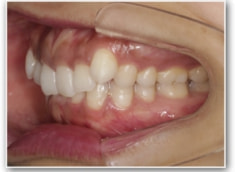

治療前